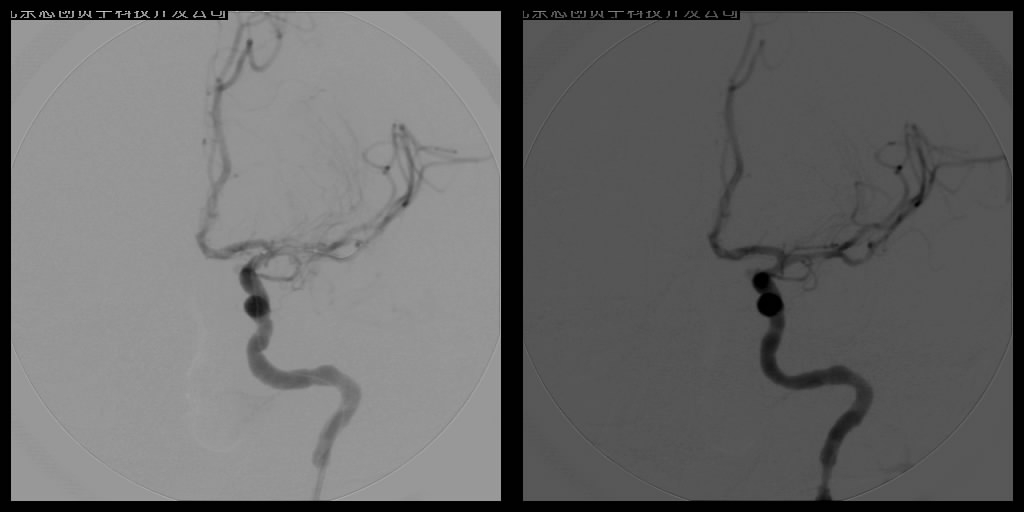

血管内溶栓及机械取栓

1.血管内动脉溶栓术

血管内溶栓有区域性动脉内溶栓、早期超选择动脉内接触性溶栓和静脉窦接触性溶栓。区域性动脉内溶栓适用于颅内大血管栓塞和血栓形成,如颈内动脉和椎-基底动脉内。早期超选择动脉内接触性溶栓适用于颈内动脉以上的各分支大小血管的闭塞和椎-基底动脉系统闭塞。